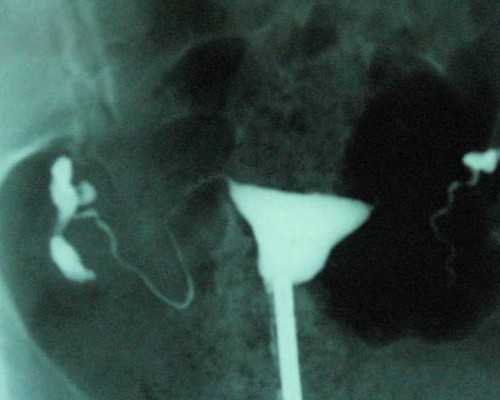

第三种是AFC,及基础卵泡。是在月经第2~5天,通过阴道B超检查双侧卵巢中小于8毫米的小卵泡数。这些卵泡是卵巢内功能性生长卵泡,数目多提示卵巢储备功能好,卵泡的正常数量应为8~10个。